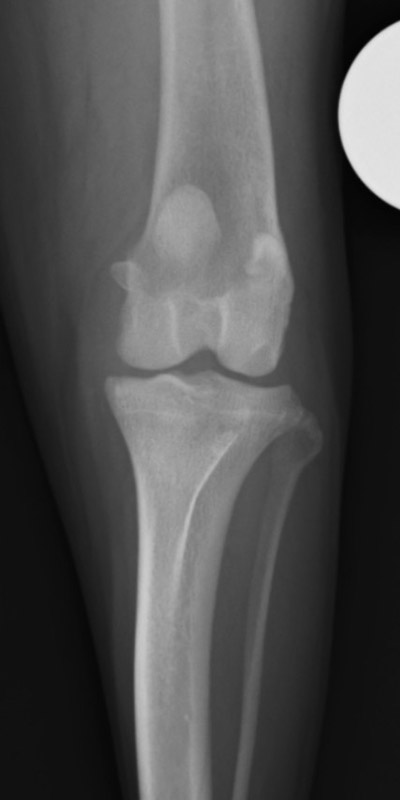

手術前

手術後

次にレントゲンの検査を行い、膝蓋骨の位置や大腿骨と脛骨に変形がどの程度あるのか、関節炎の有無などを評価していきます。